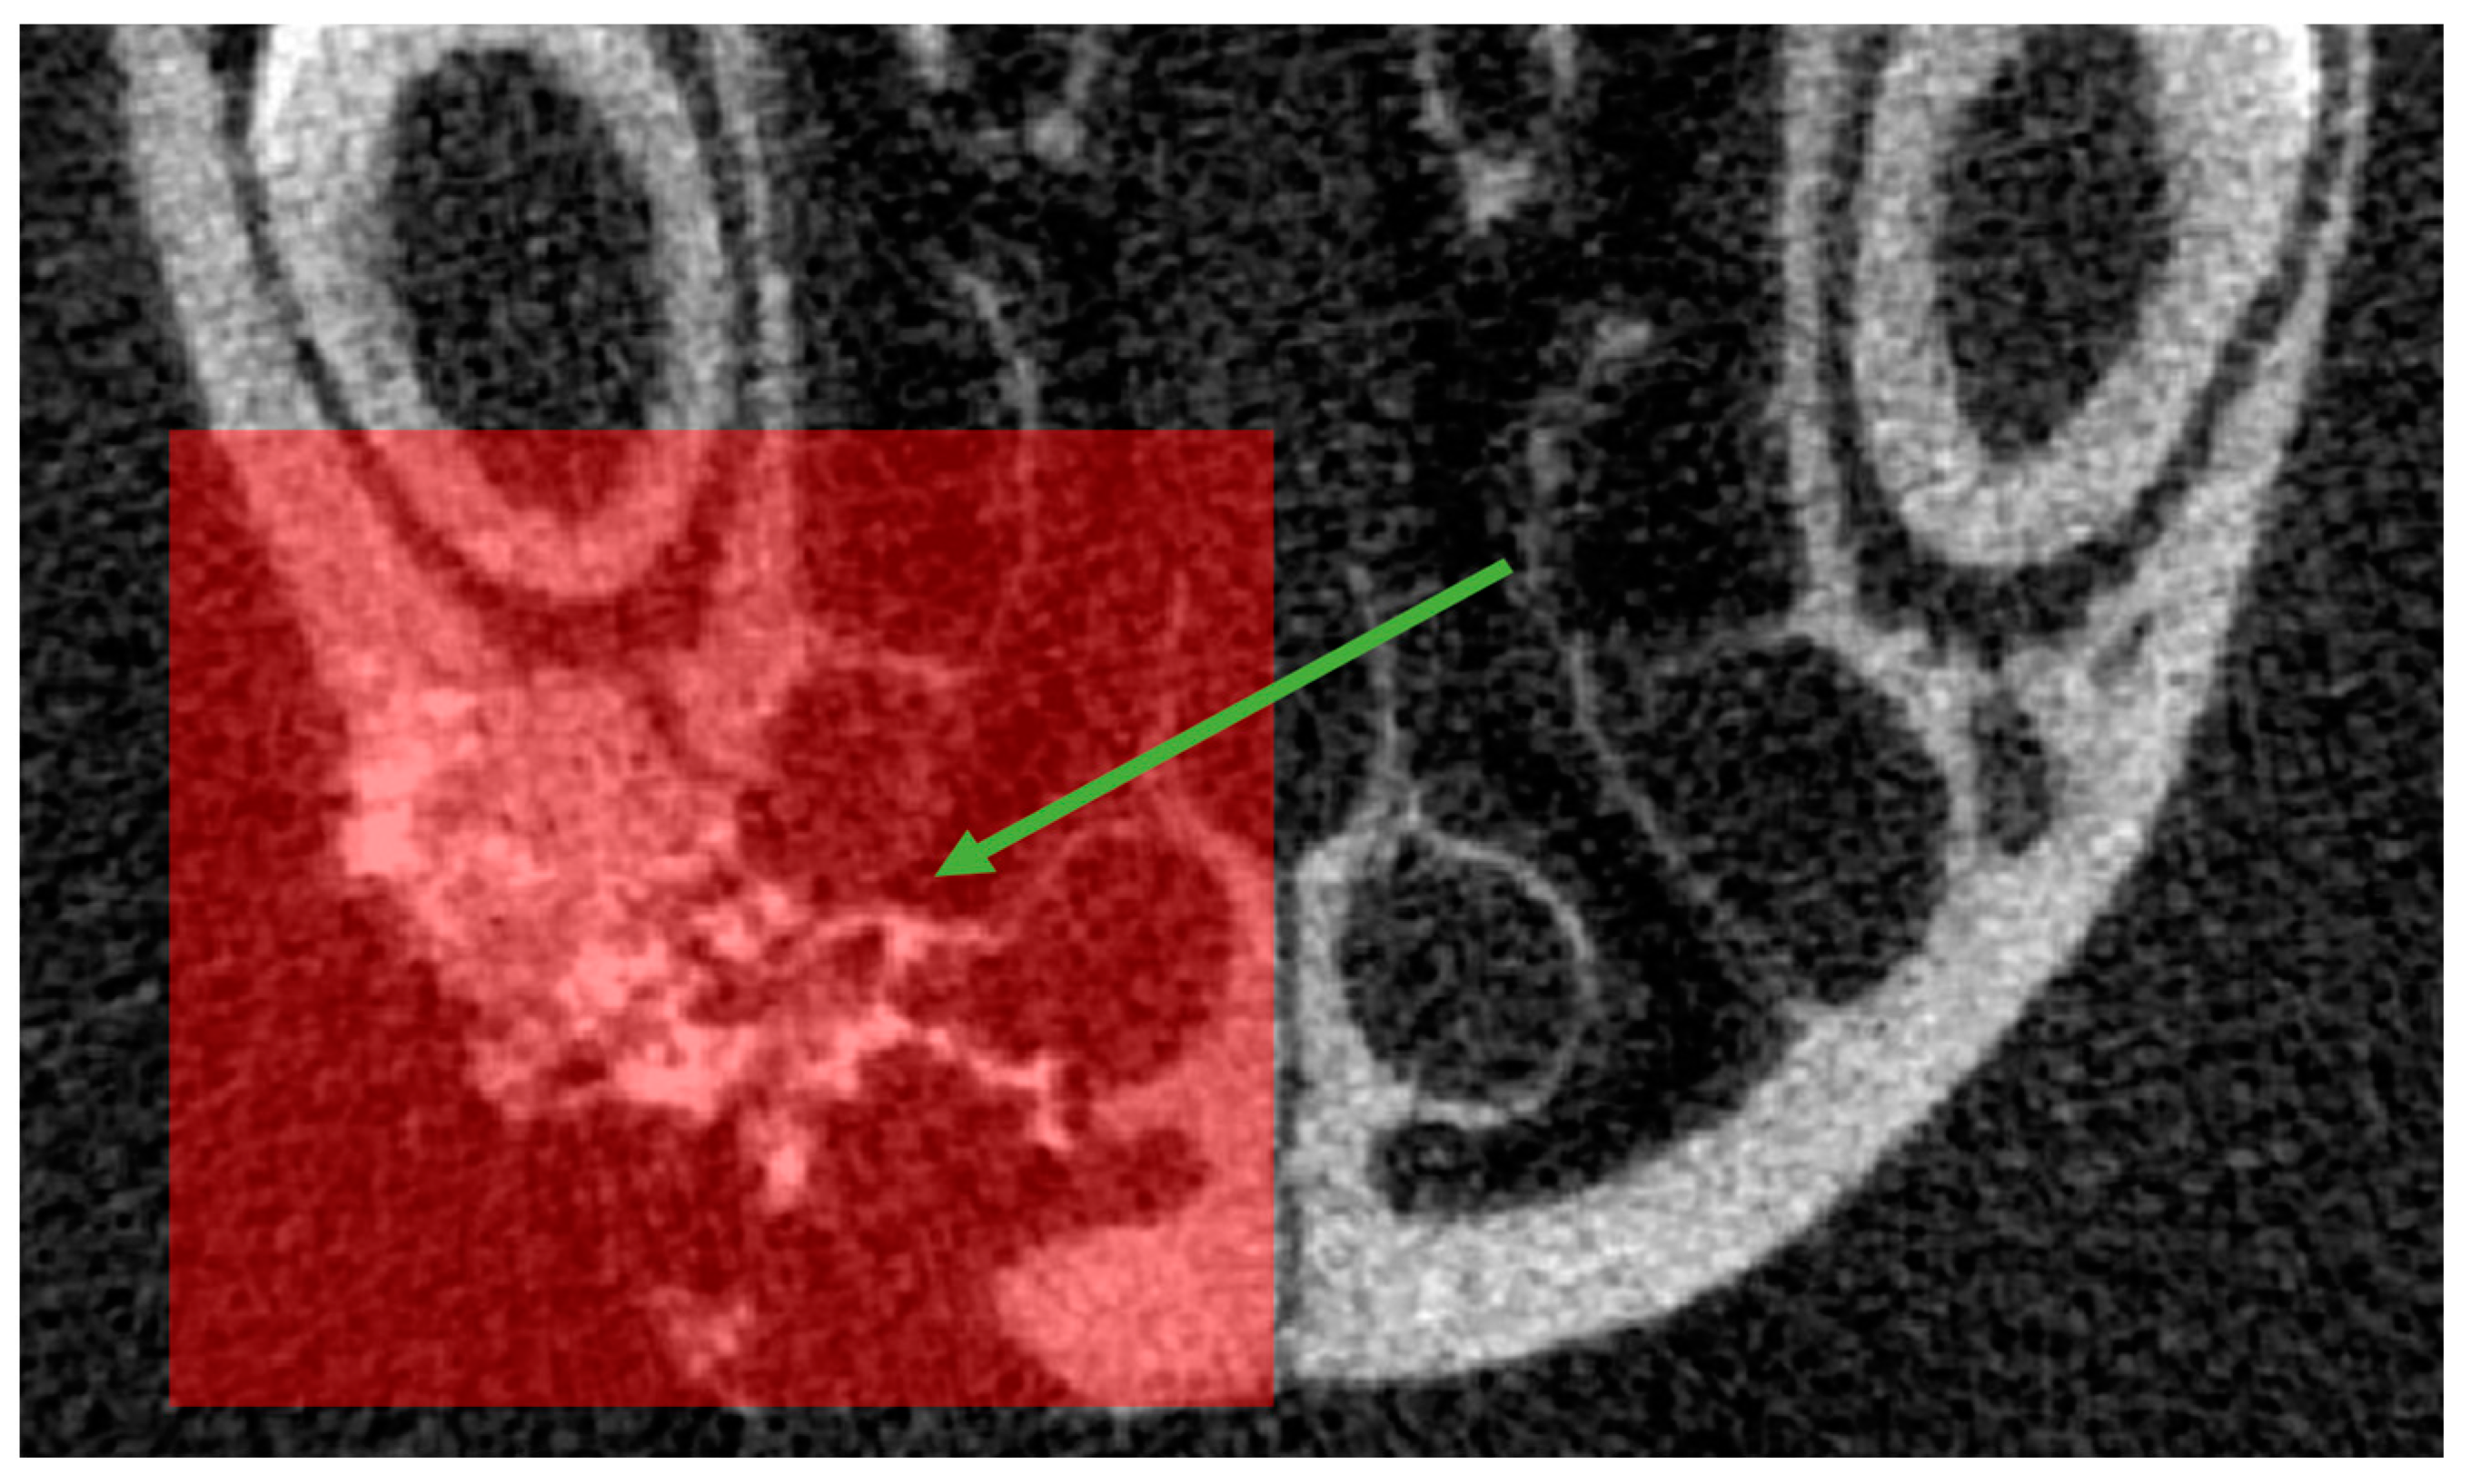

3.3.2. Computed Tomography Analysis

3.3.3. Bone Volume and Bone Mineral Density